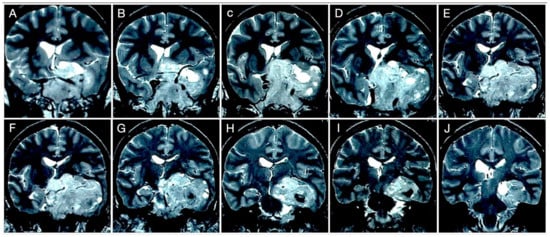

Case #8: Aggressive ACTH Tumor with Multiple Recurrences